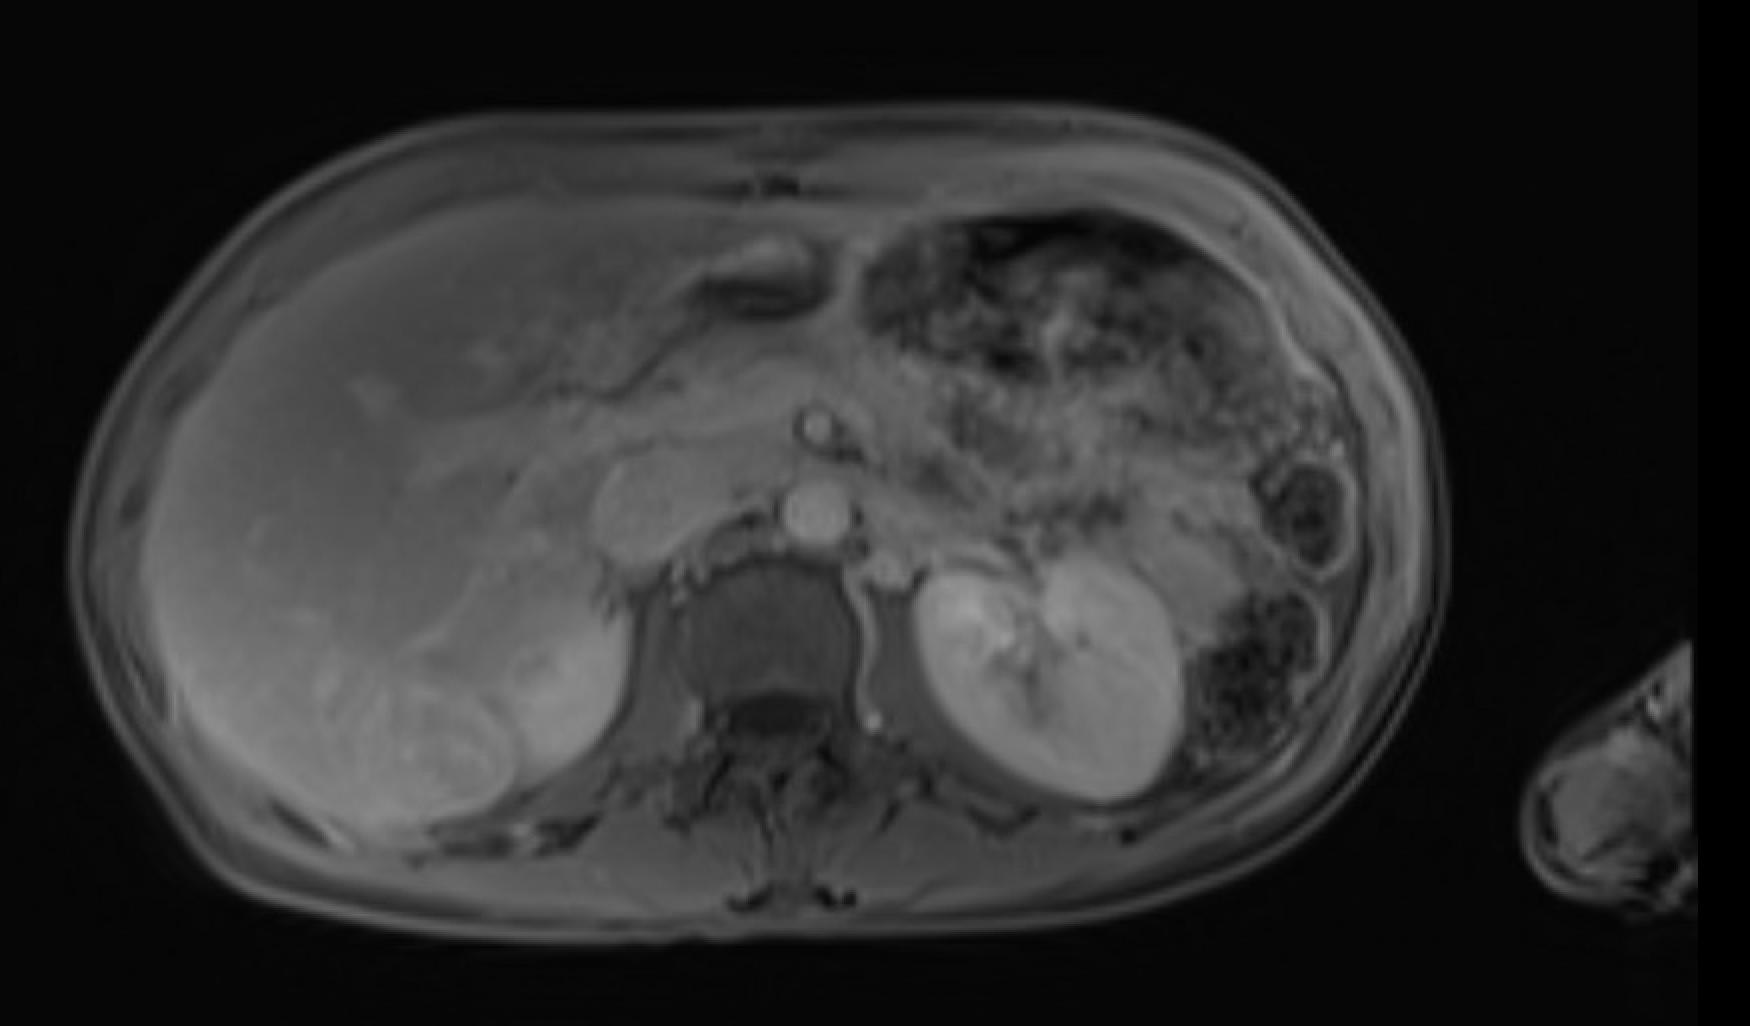

Acute interstitial edematous pancreatitis Pancreatic edema (loss of normal T1 hyperintensity) + peripancreatic fluid on T2W + preserved parenchymal enhancement on post-Gd

MRI showing acute interstitial edematous pancreatitis with loss of T1 signal and peripancreatic fluid

IEP: loss of T1 signal, preserved enhancement, peripancreatic fluid

Normal pancreas is T1-bright (brighter than liver). Loss of T1 signal = edema/inflammation. DWI restriction is sensitive for early pancreatitis. India ink artifact on out-of-phase shows subtle fat stranding